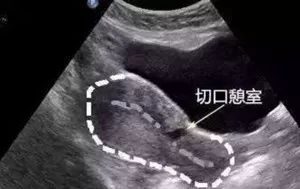

其实憩室就是B超检查发现原来剖宫产切口的位置有一个小小的“暗区”,是剖宫产切口处的子宫瘢痕上,形成一个大小不等的缺口。因憩室有子宫内膜长入其中,来月经时出血积聚在憩室中,时不时的流出一些,这也是经期延长,淋漓不尽的主要原因。

1.)经阴道三维超声(TVUS):是最简便、最常用的检查方法。典型描述就是子宫前壁下段剖宫产术后子宫切口处浆膜层连续,而肌层不连续且厚度减少,存在 1 个或数个楔形或囊状液性暗区。